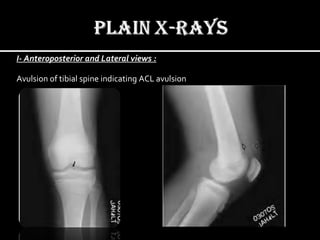

I- Anteroposterior and Lateral views :

To evaluate for fractures and/or dislocation.

Avulsion of tibial spine indicating ACL avulsion

I- Anteroposterior andLateral views : To evaluate for fractures and/or dislocation.

I- Anteroposterior andLateral views : Avulsion of tibial spine indicating ACL avulsion